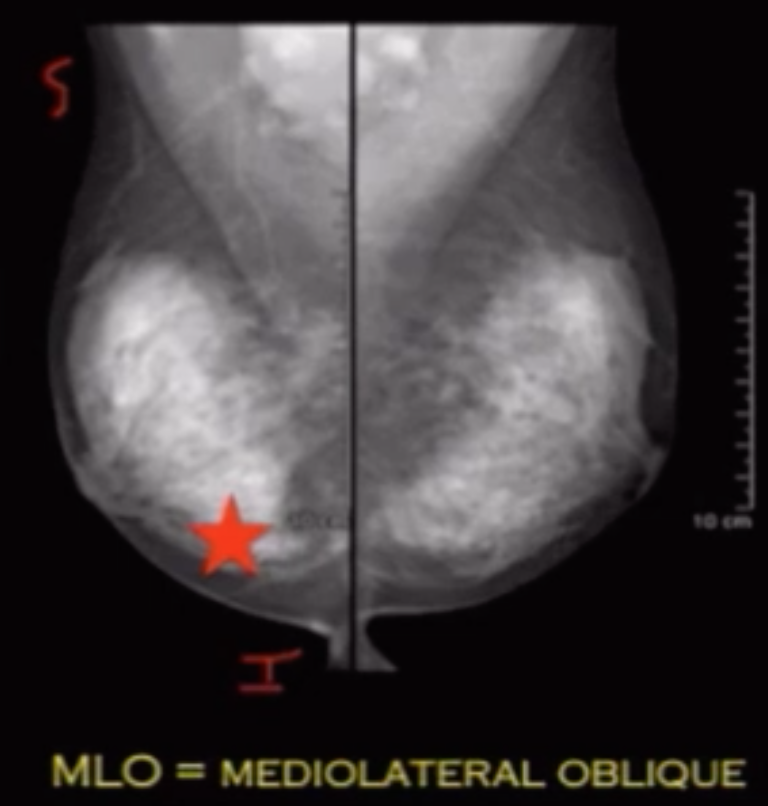

Mediolateral Oblique (MLO)

• Beam travels from superior-medial to inferior-lateral

• Draw line from nipple to border of pectus muscle = posterior muscle line

• This line needs to be within 1 cm of a line drawn from nipple posteriorly on the CC view